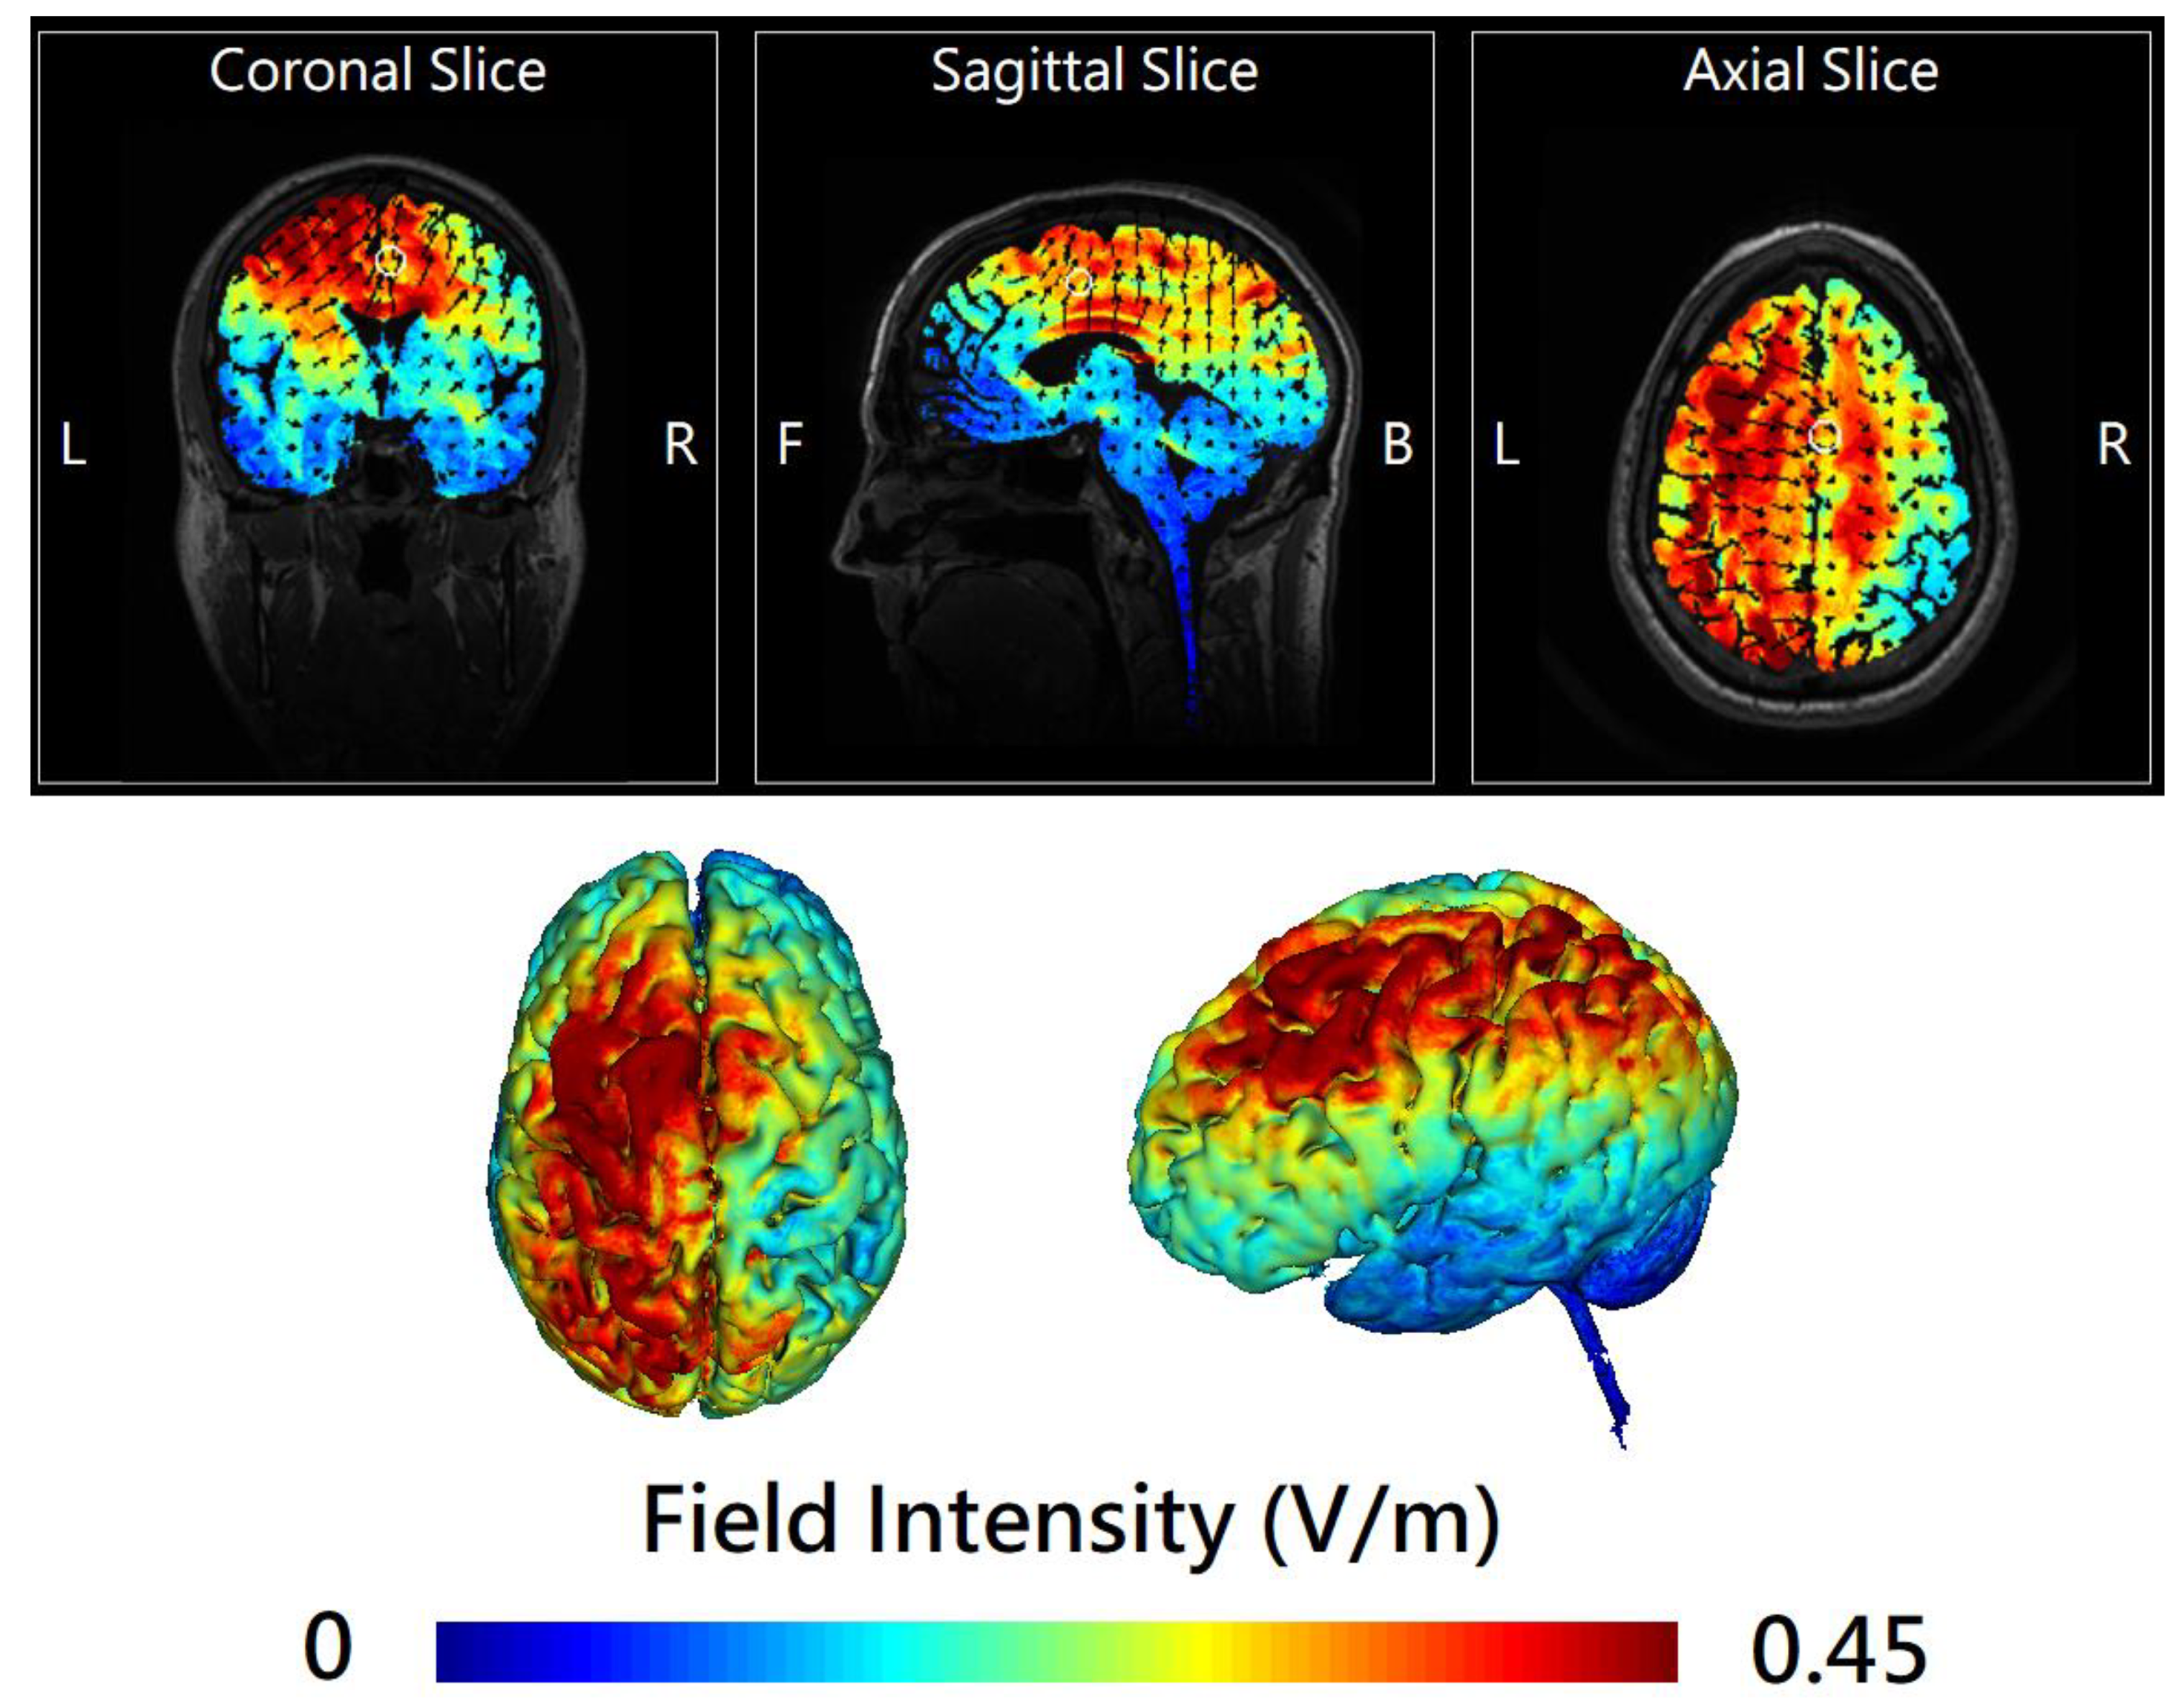

2.2. Online Left-Hemispheric In-Phase Frontoparietal Theta (6 Hz) tACS